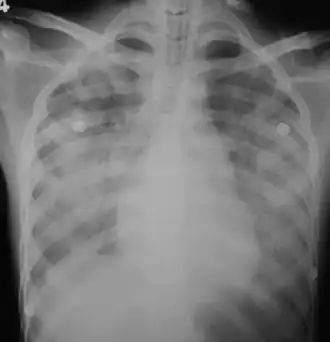

Diffuse lungs bleeding due to leptospirosis infection.

Nuwan Ranawaka, CC-BY

In those who have lung involvement, a chest X-ray may demonstrate diffuse alveolar opacities.[13]